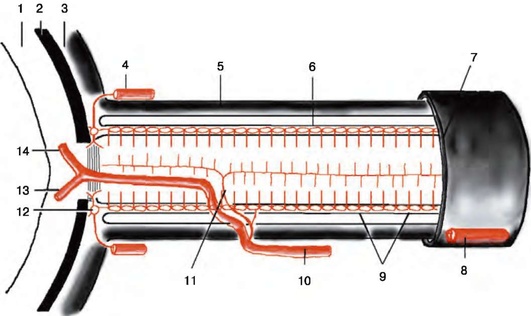

Рис. 2.2. Ретробульбарный отдел зрительного нерва и его кровоснабжение: 1 - сетчатка; 2 - хориоидея; 3 - склера; 4 - задняя короткая цилиарная артерия; 5 - твердая мозговая оболочка; 6 - мягкая мозговая оболочка; 7 - зрительное отверстие; 8 - глазная артерия; 9 - пиальное сплетение; 10 - центральная артерия сетчатки; 11 - ветвь центральной артерии сетчатки к стволу зрительного нерва; 12 - сечение галлерова или циннова артериального круга; 13 - нижняя папиллярная артерия; 14 - верхняя папиллярная артерия (по Wolff, 1948)